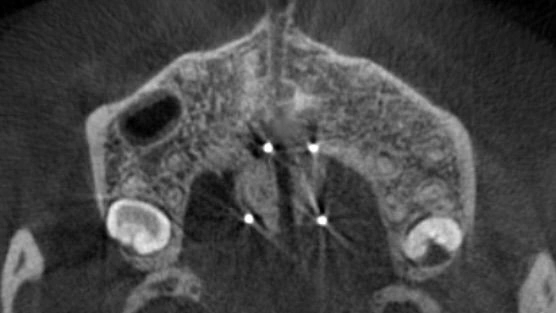

まず、MSEの中央部に正中口蓋縫合をまたぐ位置に4本の矯正用アンカーを埋入しました。浸潤麻酔で痛みなく、15分程度で処置自体は終了です。

中央部にネジを回す部分があるため、付属するレンチを患者さんに1日1回を目安に回していただきます。

初めは拡げる応力が集中するため、鈍痛を感じることもありますが、日常生活に大きな支障が出るほどではありません。

MSEの効果が出てくると、上顎の前歯部には隙間ができます。これは見た目としては我慢ポイントにはなるのですが、確実に正中口蓋縫合が離開して骨格的な拡大ができている証拠でもあるので不安になる必要はありません。

CT断面図を観ていただくと、正中口蓋縫合がしっかりと離開されています。